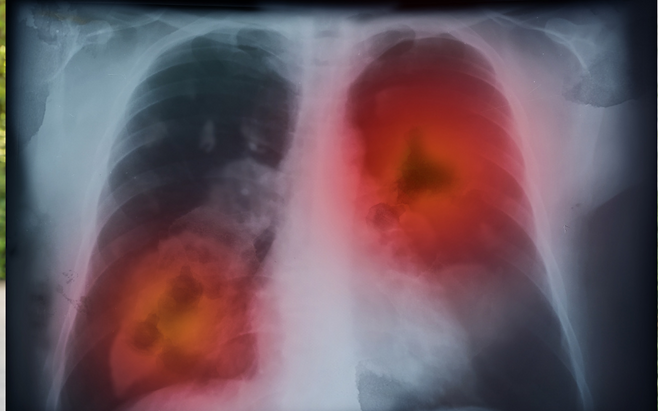

아침에 일어나면 몸 상태가 밤 동안의 건강 변화를 보여줍니다. 특히, 이 증상이 반복된다면 단순한 피로나 감기가 아니라 폐암의 초기 신호일 수 있습니다.

지금부터 폐암과 관련된 아침 증상 3가지를 알려드립니다.

폐암은 초기에 증상이 뚜렷하지 않아 이런 작은 신호를 놓치지 않는 것이 중요합니다.